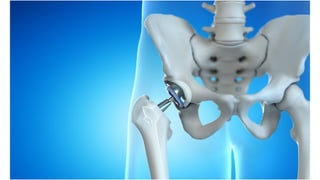

This document discusses femoral fractures, categorized by their location and severity, with classifications such as Garden classification. It outlines the types of fractures, including valgus impacted, non-displaced, partially displaced, and fully displaced, along with their surgical treatment options. Additionally, it briefly describes distal femur fractures, which occur just above the knee joint.